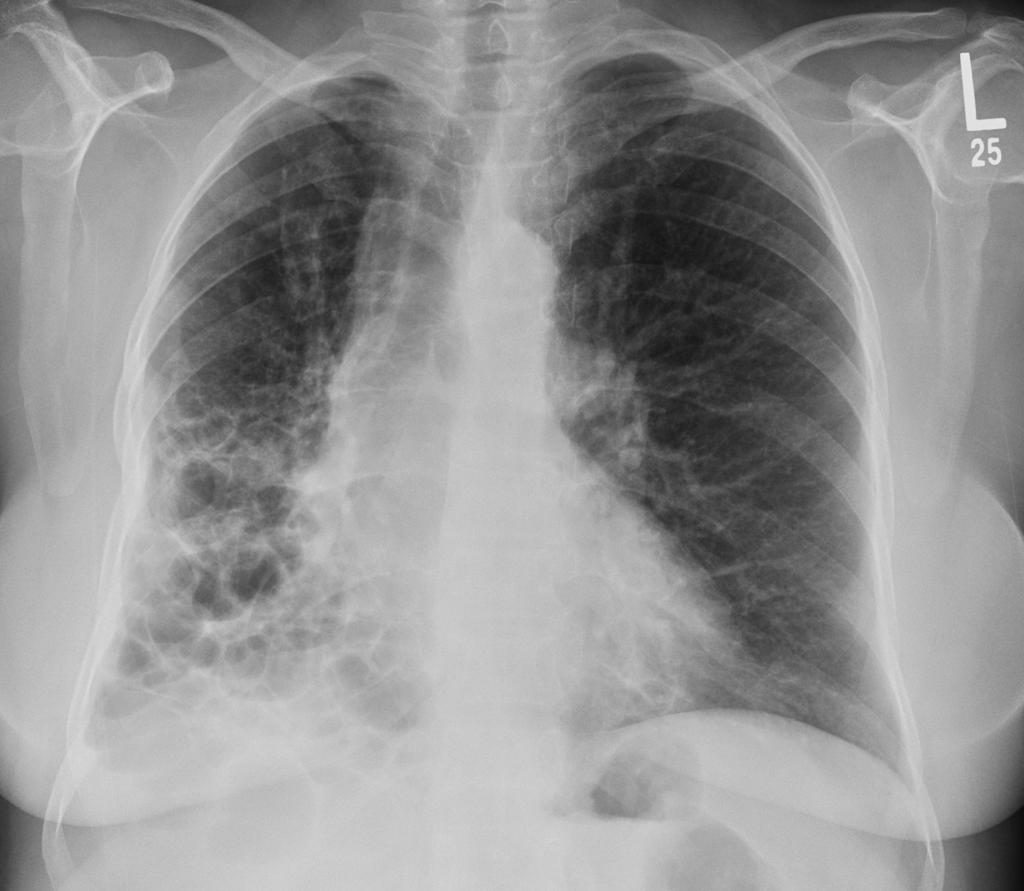

提到肺病,大多数人想到的可能是肺炎、肺癌这些"知名度"比较高的疾病,但有一类肺病却像个"隐形杀手",悄悄地损害着我们的肺部,它就是间质性肺疾病,简称ILD。 这个名字听起来就很专业,让人摸不着头脑,但实际上它离我们并不遥远。 据中华医学会呼吸病学分会统计,我国间质性肺疾病的患病率约为每10万人中有28-65人,而且这个数字还在逐年上升。 间质性肺疾病就像是肺部的"装修工人"出了问题,本来应该保持肺泡结构完整的间质组织开始"胡作非为",导致肺部纤维化、硬化,最终影响呼吸功能。 听起来有点可怕,但别慌,了解了它的"脾气",我们就能更好地应对。

但当间质组织发生炎症、纤维化时,这堵""就变厚变硬了,气体交换就困难了

当这些部位发生炎症、纤维化时,就会影响肺部的气体交换功能